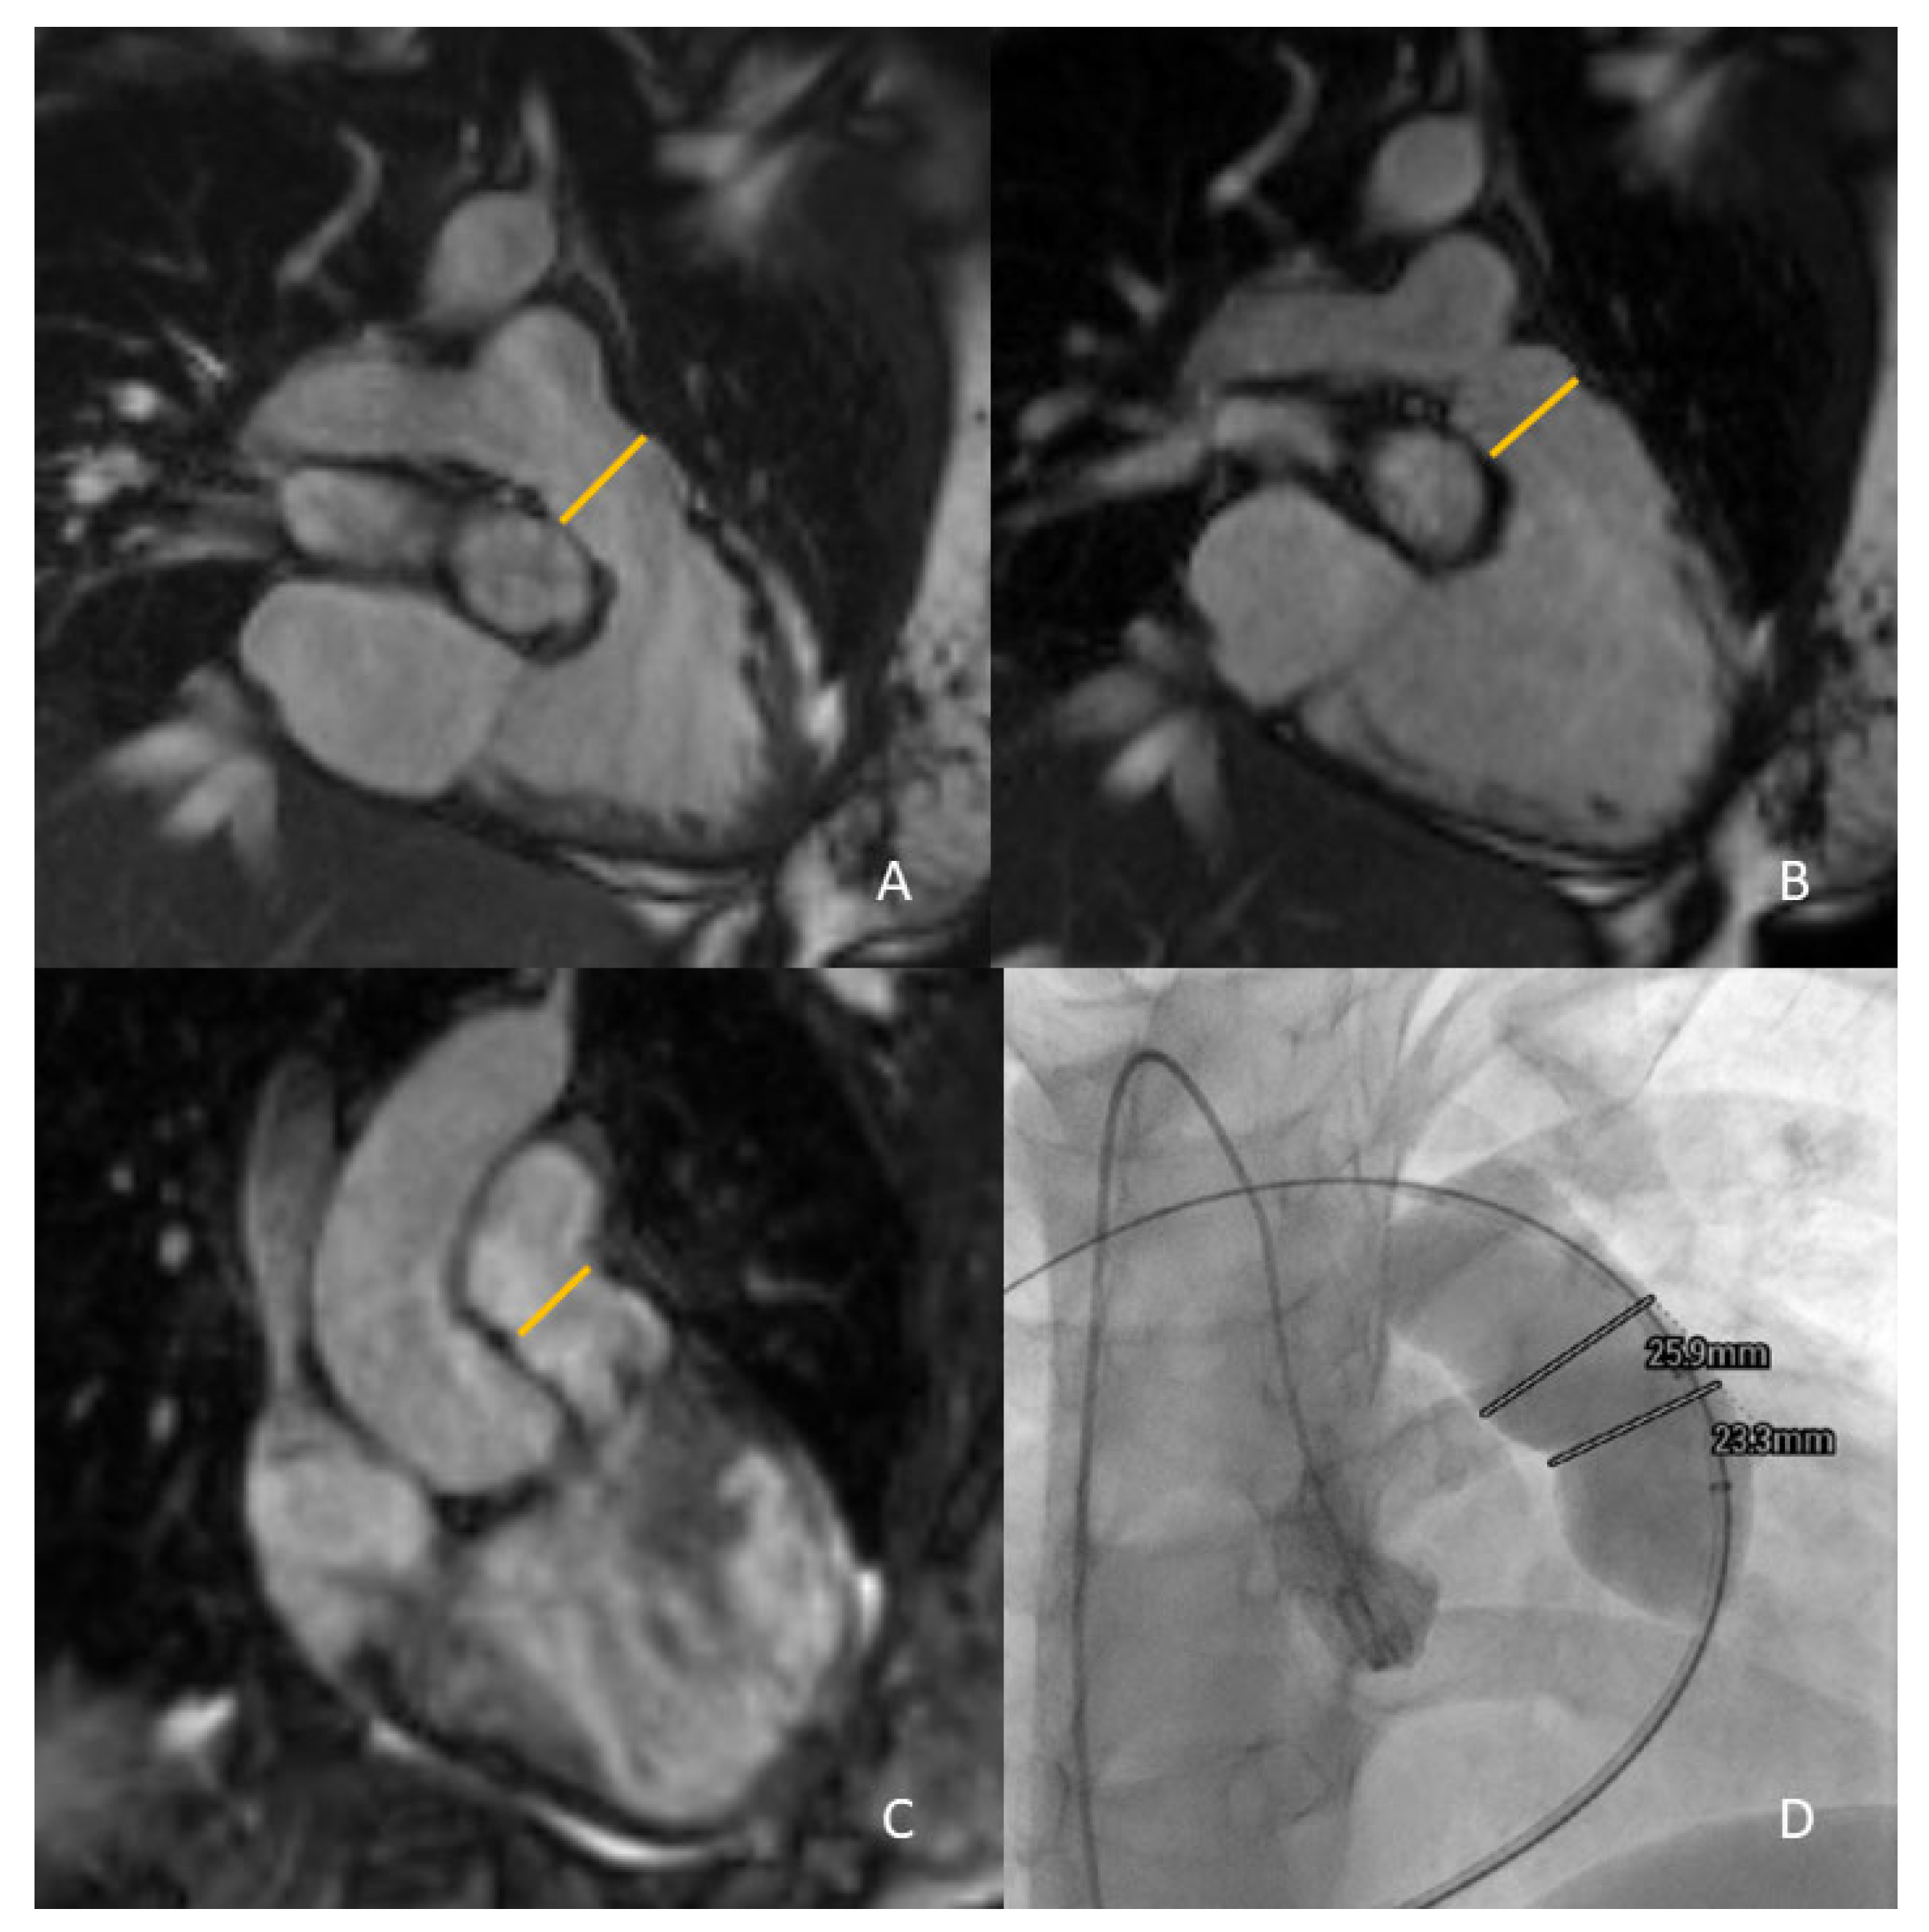

For the RVOT anatomy, different anatomical CMR sequences can be performed, such as contrast-enhanced MR angiography (ceMRA) and 3-dimensional (3D) whole-heart sequences (Figure 3).

Figure 3.

Measurement of the RVOT by CMR for PPVI feasibility and valve sizing: 2D cine views at end-systole and end-diastole ((A) and (B), respectively), and 3D whole heart imaging sequences (C). Final check of CMR data with invasive angiography (D).

The different timings of image acquisition between 3D whole-heart and ceMRA inevitably introduce a clear difference in RVOT measurement. Ferrari et al. compared RVOT measurements by ceMRA and 3D steady-state-free-precession (SSFP) sequences at end-systole (ES) and end-diastole (ED) in a retrospective study of 31 CHD patients with moderate to severe PR, in native or patched RVOTs and significant RV dilatation. This study demonstrated that 3D SSFP diameters at ES were significantly higher than those taken at ED and with ceMRA. In this study, ES diameters with whole-heart imaging also showed the best agreement with cardiac catheterization data [34]. A study by Leonardi et al. evidenced that RVOT measurements by 3D SSFP sequences acquired at ES were able to identify the ideal candidates for PPVI when compared to sequences acquired in mid-diastole in operated TOF patients.

Moreover, ES data showed the best correlation with cardiac catheterization to quantify RVOT dilatation. In contrast, mid-diastolic measures seemed to underestimate the RVOT size when compared to angiographic data [37]. In another study, Ebel et al. showed that the maximum and effective RVOT diameters acquired in 3D SSFP at ES had the best agreement with invasive balloon sizing and presented an optimal image quality and reproducibility against ceMRA [33].